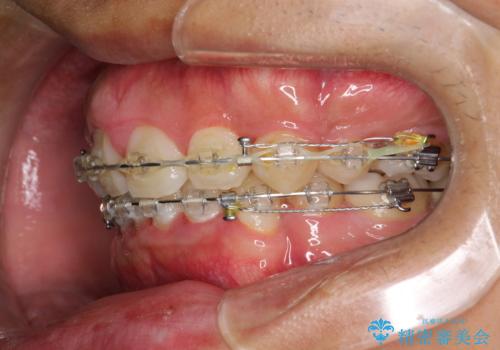

ワイヤー矯正終了時に装置除去と合わせてPMTC

- ワイヤー矯正の終了時にしばらく行っていないためクリーニングも希望されました。装置の除去j時にPMTC60分コースを行いました。

装置を除去すると、エナメル質にダメージがかかることなどがあります。除去の際、一緒にクリーニングを行うことで、エナメル質をなめらかにしたり、歯ぐきの引き締まりが見られます。また、歯ブラシだけでは取り除けない汚れも取り除きますので、歯の表面がツルツルになります。矯正治療中・終了時には合わせてPMTCを行うことがおすすめです。